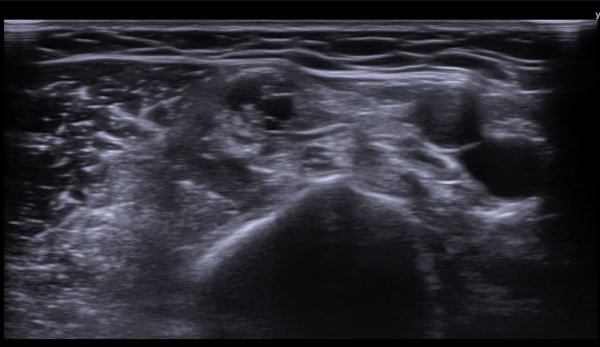

(»çÁø 1, 2). ŽÃËÀÚ¸¦ Á¶±Ù ´õ ±ÙÀ§ºÎ·Î À̵¿ÇÏ´Ï Á¤Á߽ŰæÀÇ Àú¿¡ÄÚ ºÎÁ¾ÀÌ °üÂûµÈ´Ù(»çÁø 3, 4).

Á¤Á߽Űæ Ⱦ´Ü¸é°Ë»ç¿¡¼­µµ Á¤Á߽ŰæÀÌ Àú¿¡ÄÚ ºÎÁ¾ÀÌ ±æ°Ô  °üÂûµÇ°í ½ÇÁú³» ƯÁ¤ ¼¶À¯¼ÒÀÇ

Àú¿¡ÄÚ ºÎÁ¾ÀÌ ¶Ñ·ÇÇÏ´Ù(»çÁø 5, 6).